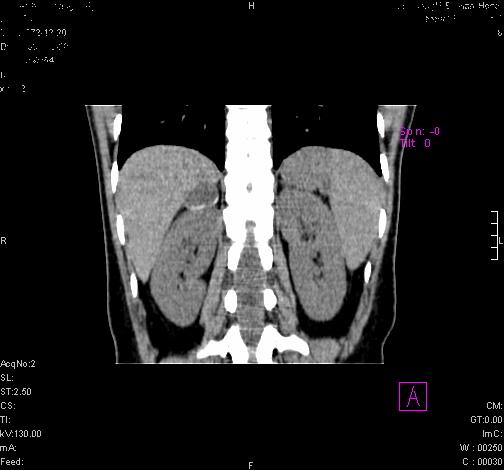

标题: CL0340:【】肾上腺囊肿,比较典型。

患者为年轻女性,查体发现右侧肾上腺囊性占位。无临床体征。

这么漂亮的图像,一看一目了然。典型的右侧肾上腺囊肿,周围有钙化。感谢搂主!

这么明显的弧形钙化,多考虑包虫病所致的寄生虫性囊肿。

右侧肾上腺囊性密度灶囊壁有钙化。考虑肾上腺囊肿,结核?